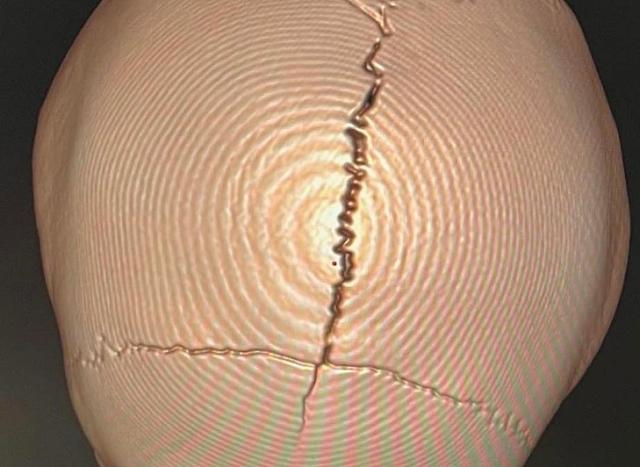

Πραγματικό σοκ προκαλεί η εικόνα του σπασμένου κρανίου ενός 5χρονου παιδιού που παρασύρθηκε από διερχόμενο όχημα ενώ διέσχιζε την εθνική οδό έξω από το ξενοδοχείο όπου διέμενε με την οικογένειά του, δημοσιοποιεί με ανάρτησή του, ο νευροχειρουργός του νοσοκομείου Χανίων Αντώνης Κρασουδάκης, καταδεικνύοντας τα κακώς κείμενα στον τομέα της οδικής ασφάλειας στην Κρήτη, που αναπόφευκτα επηρεάζει το τουριστικό μας προϊόν.

Ο γιατρός δημοσιεύει δύο φωτογραφίες.

Στην πρώτη απεικονίζεται το σπασμένο κρανίο του παιδιού που νοσηλεύτηκε μέσα στον Αύγουστο μετά την παράσυρσή του, αργά τη νύχτα, "κάτω από αδιευκρίνιστες συνθήκες", όπως αναφέρει χαρακτηριστικά.

(το κεφαλι του παιδιού μετά το τροχαίο)